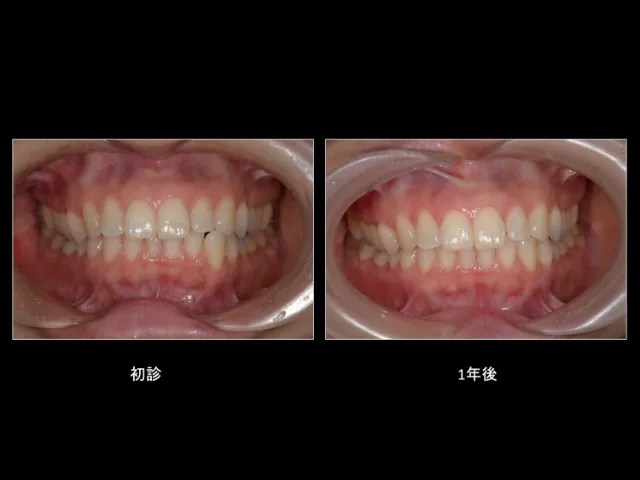

マウスピース型矯正歯科装置 ~目立ちにくい矯正治療~

従来のブラケット(金属の装置)を歯に付ける矯正方法とは異なる、透明なマウスピース型の矯正装置です。

マウスピース型矯正歯科装置は、透明なアライナーというマウスピースを使用し、少しづつ歯を移動します。